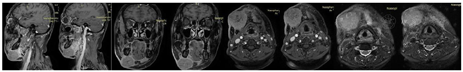

辅助检查:MRI提示右侧颌下软组织肿胀,渗出,邻近皮肤增厚,双侧颈部IB区多发小淋巴结,较大者为右侧,短径41 mm(图1)。病理提示颌下软组织非角化性未分化癌,免疫组织化学(Immunohistochemistry,IHC):P63(+),CK5/6(+), EGFR(+),S-100(个别细胞+),SOX10(-),P53(70%+), Ki-67(80%+)。EBV-EBER部分+。Epstein-Barr病毒(EB virus, EBV)脱氧核糖核酸(deoxyribonucleic acid, DNA) 7.58×103 copies/ml。

外科会诊考虑手术难度大,需整形科协助,且患者不同意手术。于2021年5月至2021年8月行4周期吉西他滨+顺铂方案(GP方案)化疗联合特瑞普利单抗免疫治疗。